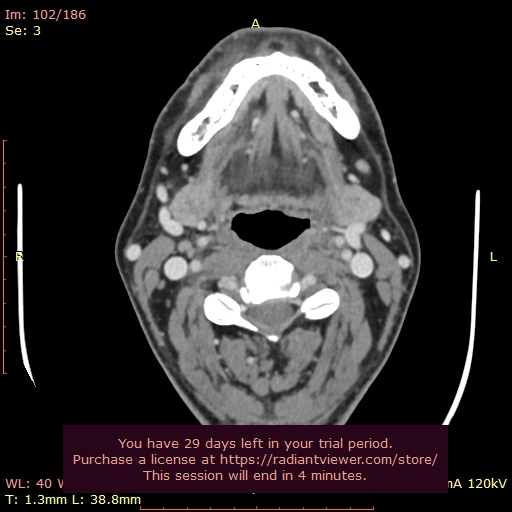

Eventually, I was diagnosed with Eagle Syndrome and had intraoral surgery here in Spain to shorten both styloids. The surgeon reduced them a lot (between 1,5 and 2cm left), but unfortunately my symptoms did not resolve. In fact, they shifted in character. Since then, I’ve been caught in between two possibilities:

Misaligned hyoid bone (the greater horn sitting too high or angled, possibly pressing on nerves or vessels).

This has made things very confusing, since the CT scans show both structures could be implicated. Sometimes I feel like my jaw and face don’t “fit” together, as if something needs to click into place, and other times I feel choking sensations at the hyoid level, especially when there’s mucus or throat irritation.

So now I’m stuck between wondering if my symptoms are due to what remains of the styloid, or if it’s actually the hyoid bone causing the problems.